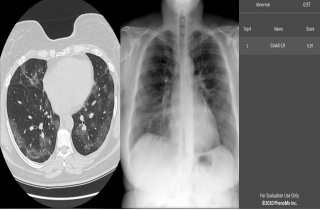

±¹»ê Äڷγª ÀΰøÁö´É(AI) Áø´Ü ¼­ºñ½º, Ú¸ ÁøÃâ

[»çÁø¼³¸í : ÀΰøÁö´ÉÀÌ ÆóCT ¹× X-RAY ¿µ»óÀ» ÅëÇØ ½ÅÁ¾ Äڷγª¹ÙÀÌ·¯½º ħ¹ü ¼öÄ¡¸¦ Á¦½ÃÇÑ °á°ú] [µ¥Àϸ®¸Þµð ÀÓ¼ö¹Î ±âÀÚ]2020-04-05 13:51:28